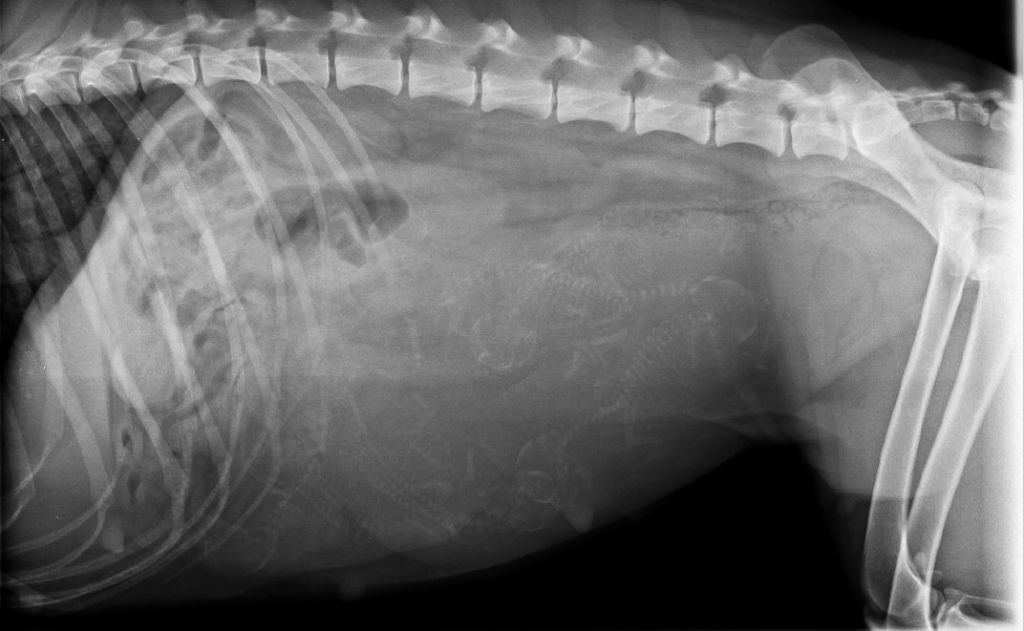

RADIO DE FIN DE GESTATION

Nous y sommes ! En avant première, je viens de voir d'adorables petits bébés Whippet.

Mon dieu! Comme c'est beau la vie ! j'en ai toujours le...